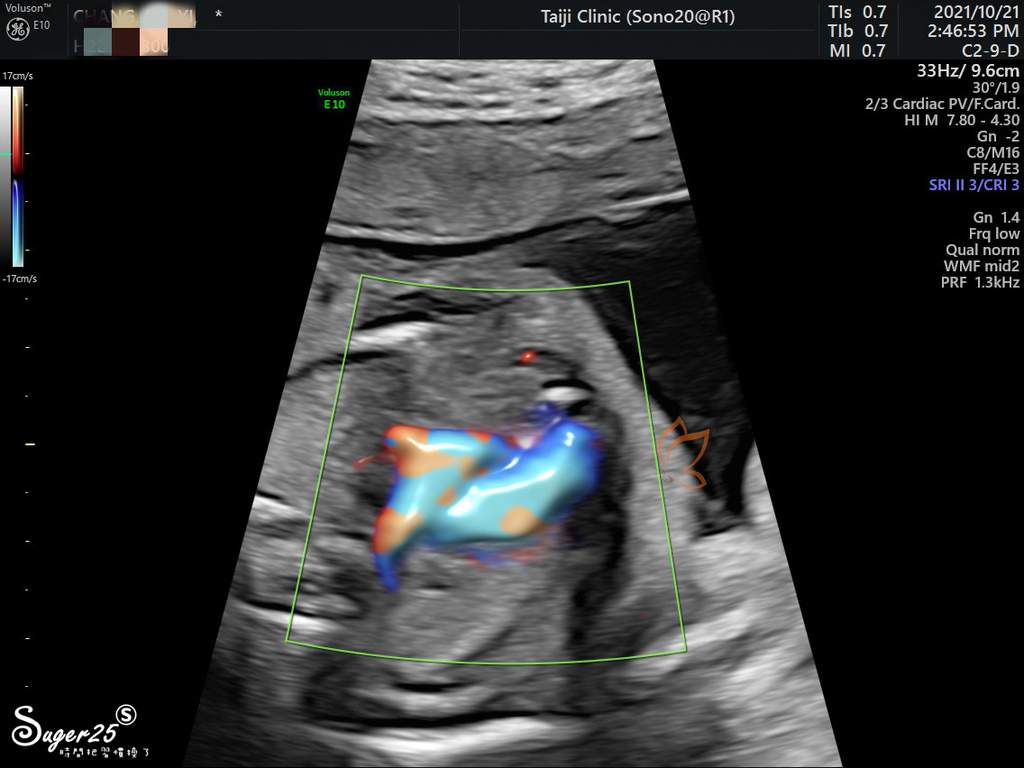

器官血液靜脈動脈之類的畫面